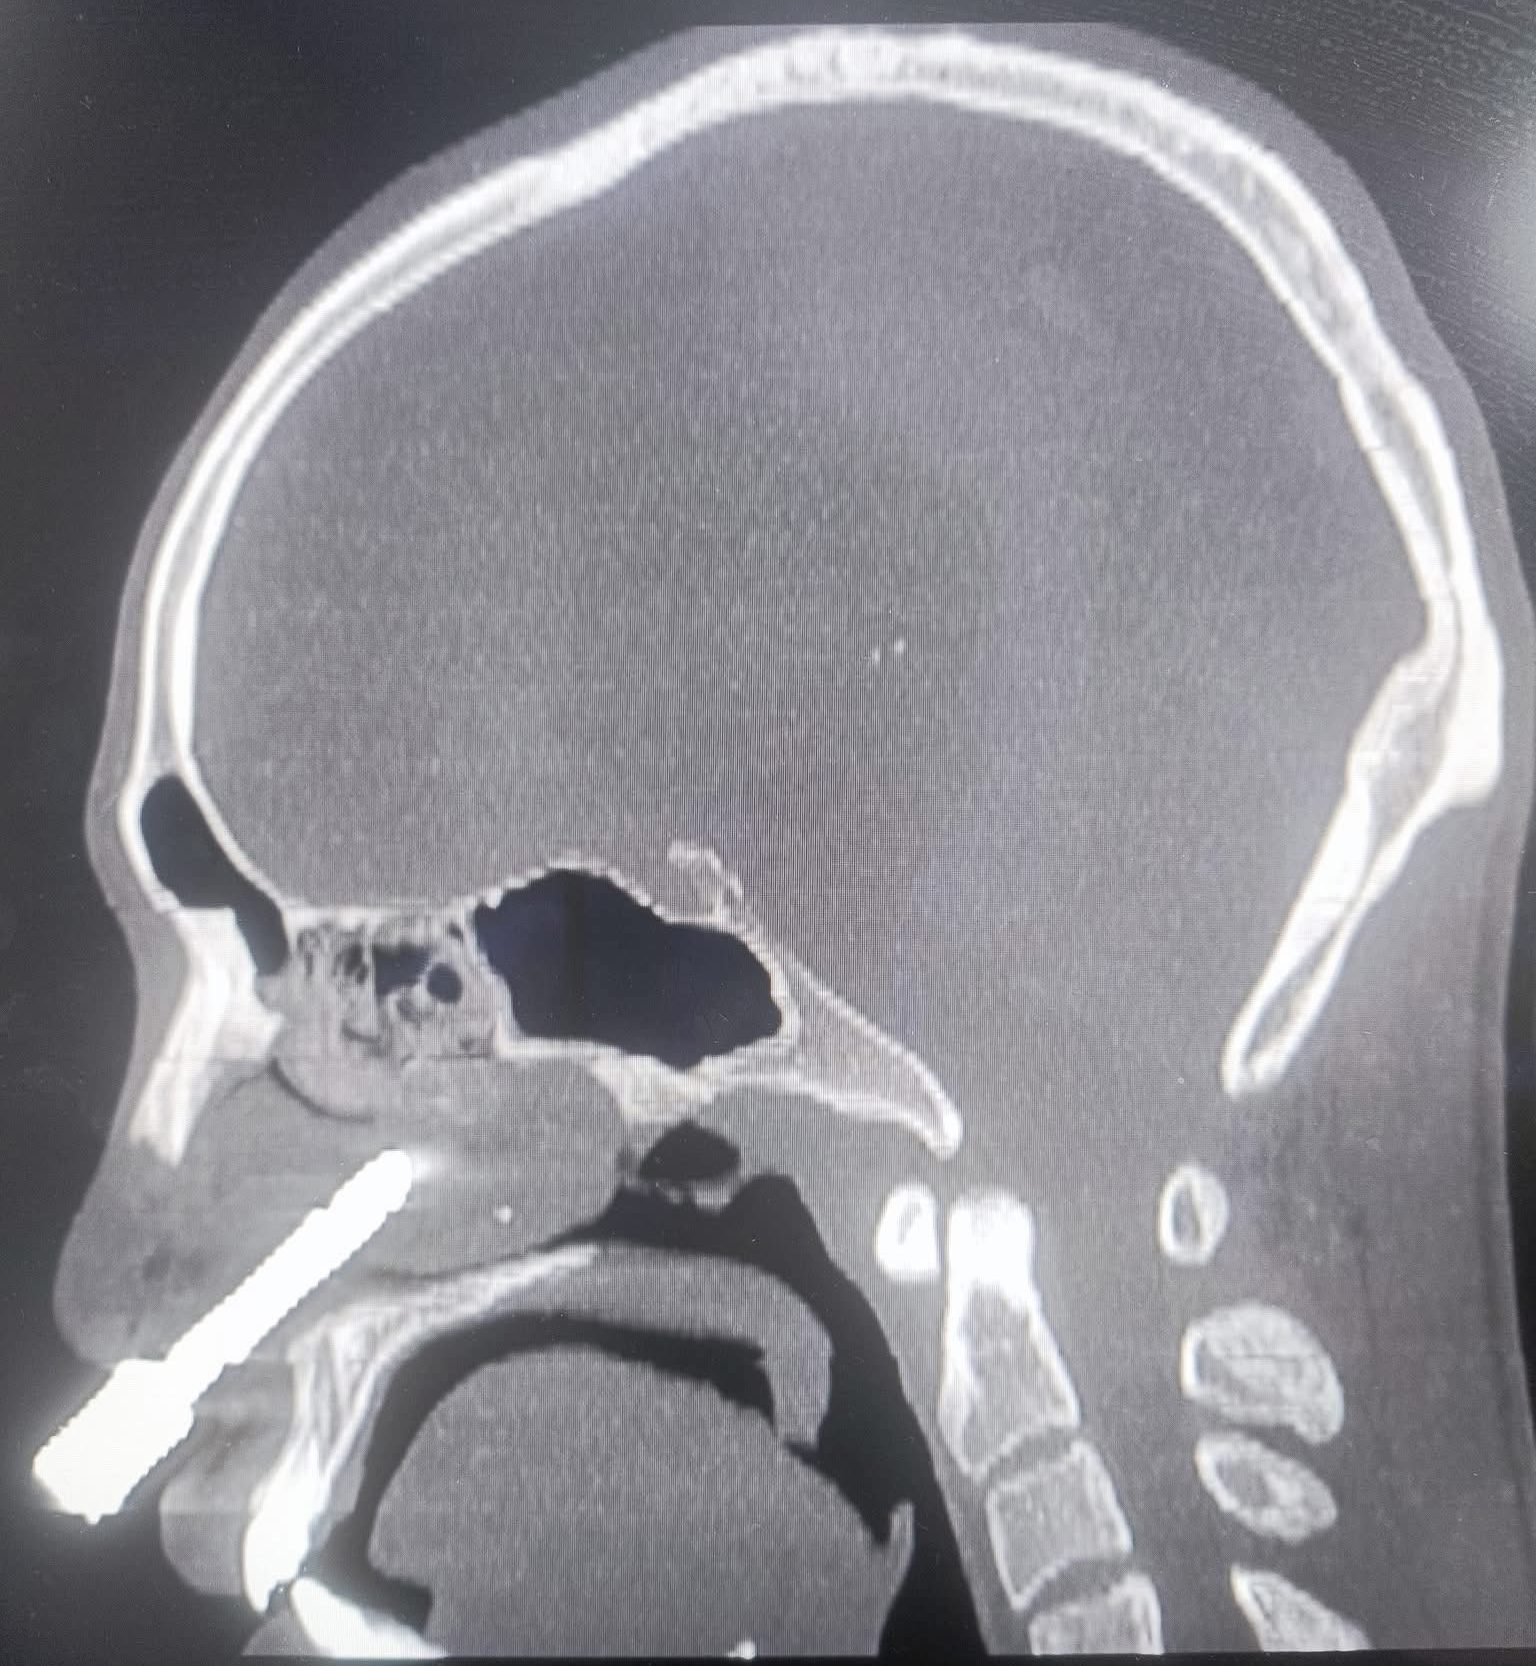

Hình ảnh dị vật cắm sâu vào hốc mũi bệnh nhân trên phim chụp CLVT

Kết quả chụp cắt lớp vi tính (CT-Scan) và dựng hình ảnh 3D cho thấy: dị vật là một mũi khoan kim loại dài khoảng 7–8cm, có hình cong như lưỡi câu, đâm từ hốc mũi phải xuyên thủng hoàn toàn vách ngăn mũi, đầu móc cong cắm sâu vào hốc mũi trái. Phần cuống mũi dưới bị rách nặng, toàn bộ vách ngăn bị thủng lớn. Trước tình trạng tổn thương phức tạp, bệnh nhân được chỉ định phẫu thuật cấp cứu ngay lập tức.